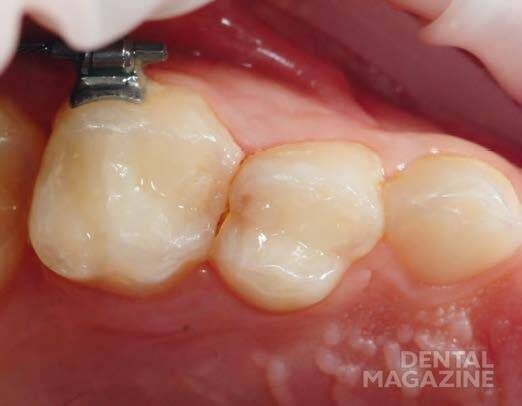

Как и многие взрослые, большинство юных пациентов и пациенток далеко не всегда получают удовольствие от пломбирования и часто не готовы к сотрудничеству. Поэтому лечение нужно проводить достаточно быстро. Ниже на примере конкретного клинического случая мы рассмотрим эффективную технологию пломбирования молочных зубов с помощью Tetric EvoFlow Bulk Fill (рис. 1).

Рис. 1. Исходная ситуация: зуб 54 с дистальным кариесом.

Для обеспечения чистоты и относительной осушки операционной области используется держатель для губ и щек OptraGate®. Он помогает удерживать полость рта ребенка открытой и отводит мягкие ткани от зубов. Для дополнительной осушки можно использовать ватные тампоны. После препарирования поврежденного зуба и удаления кариеса устанавливается подходящая матрица (рис. 2). В качестве адгезива применяется Adhese Universal. После нанесения он сушится потоком воздуха и отверждается светом (рис. 3). Затем проводится пломбирование полости композитом Tetric EvoFlow Bulk Fill (рис. 4). Канюля аппликатора устанавливается на дно полости, материал выдавливается, и канюля медленно поднимается к поверхности. Эта техника позволяет предотвратить образование пузырей. Tetric EvoFlow Bulk Fill отличается великолепной растекаемостью.